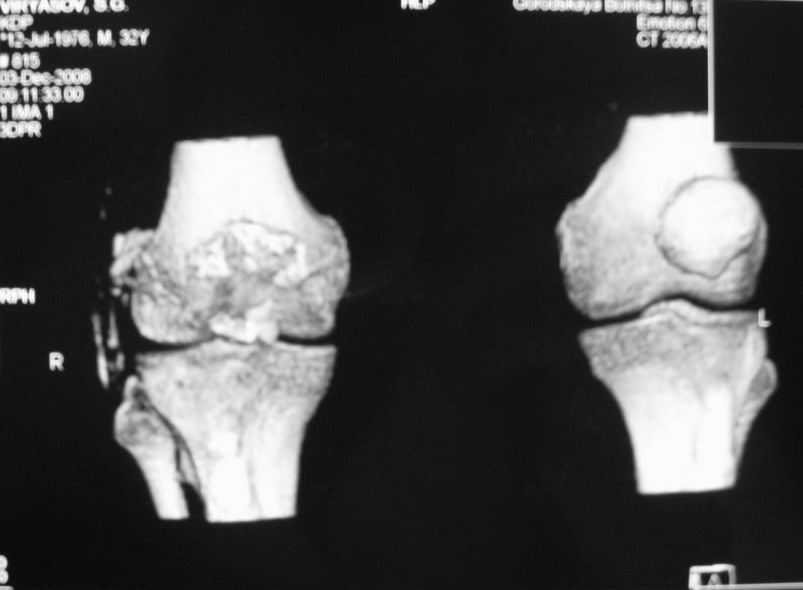

Уважаемые коллеги! Обратился пациент 32 лет с травмой коленного сустава от июля 2008 года - падение с мотоцикла, прямой удар передней поверхностью коленного сустава. Диагноз - открытый оскольчатый перелом надколенника. В одной из больниц города выполнили ПХО, шов надколенника лавсаном. Заживление раны с частичным нагноением(разведена на участке 3 см).

Сейчас мягкие ткани в порядке. R-снимки, КТ в приложении. Объем движений 0/0/110 гр.Ходит почти без хромоты.

Жалобы на торчащий под кожей один из отломков, боль в этой точке.Вопрос: что делать? Первое - убрать этот отломок и на этом закончить. Второе - оставить все как есть(отломок не так уж и сильно мешает). Ждать возможного развития артроза, дальше по ситуации. Третье - подумать о протезировании надколенника.